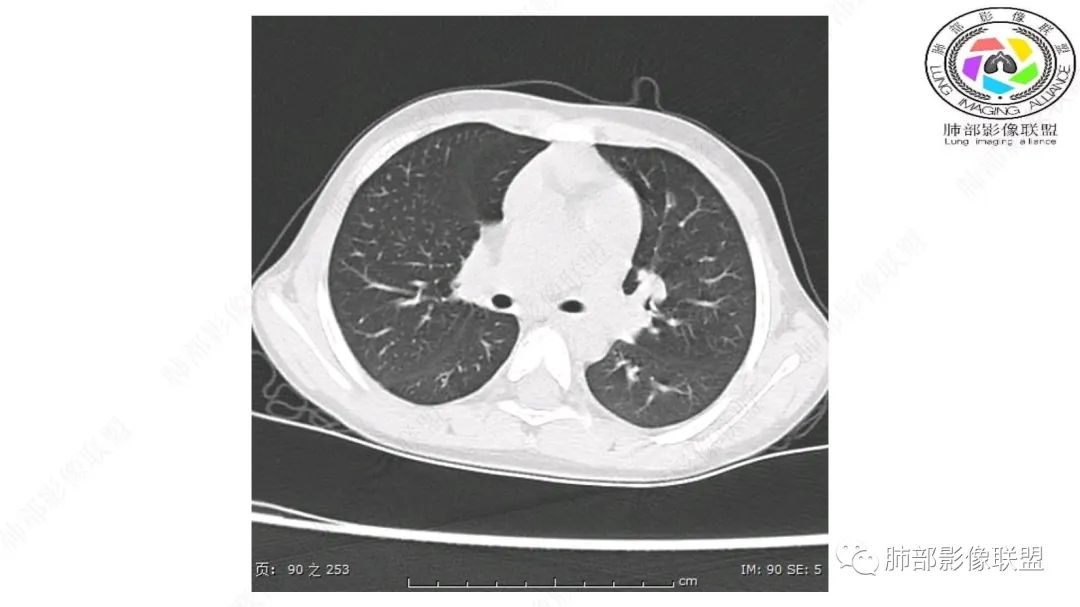

患儿3岁 咳嗽检查发现纵隔占位。右肺上叶受压表现,占位以脂肪组织密度为主,似见分隔,首先考虑为脂肪母细胞瘤,鉴别脂肪瘤,畸胎瘤。

定位:肺内?尖段气管未见明显显示,腔静脉受压向右推移?病灶内可见前段动脉穿行,脂肪密度为主。

肿块起源于右上气管分叉处?强化动脉血管最后汇入右肺动脉上干。

右侧纵隔奇静脉水平起源?压迫上肺,包绕动脉?

跨肺门,包绕肺血管分支,邻近肺组织受压肺不张。

第一个问题:定位:肺内?纵隔?

病灶属于交界区,主体位于肺内,占位效应明显,前方突入胸壁,胸腺受压变形,胸膜显示欠清楚;病灶包绕上叶肺动脉;似乎有体动脉供血。符合肺内的点:包绕上叶肺动脉分支;符合纵隔的点:前方似乎突入胸壁,与胸腺关系比较密切,但是与上腔静脉的关系提示病灶不支持纵隔来源,前纵隔的常规会将上腔静脉受压后移、外移,这是不符合的。

从这个角度符合肺内的,有一点不太踏实的是:似乎突入前胸壁。

1.右上肺-纵隔交界区巨块影,主体位于右肺一侧,紧贴胸腺、头臂干、右锁骨下动脉、上腔静脉、奇静脉等,不能分离,但病灶整体边界清楚。注意上述相邻腔静脉等结构未见受压变形,纵隔亦未见明显向左推移,至少提示两点:

2.肺动脉穿行也许是肺内来源最重要支持点!